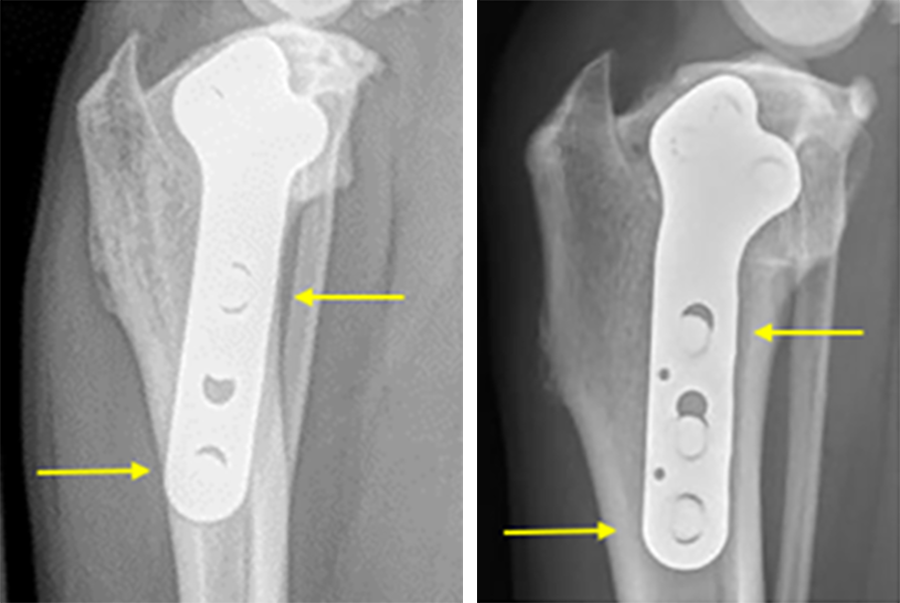

Case 1: Bentley Hoe, male neutered Golden Retriever, 32 kg

(Case provided by Alexis Bilmont, West Midlands, England)

A 32 kg male neutered Golden Retriever presented with a recent deterioration of chronic right hind limb lameness. Physical examination revealed a cranial cruciate ligament rupture.

Follow-up x-rays at 8 weeks postoperatively revealed stable implants, stable bone segments, and healing of the osteotomy. The clinical outcome was satisfactory.